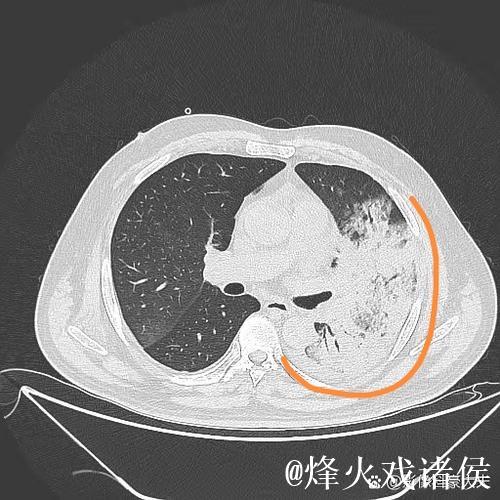

肺炎之所以让人恐惧,不仅因为它可能引发呼吸衰竭,甚至威胁生命,更因为它在短时间内剥夺了一个人对自己身体的信心。高烧、胸闷、呼吸困难,让人感到前所未有的无助。埃迪豪在住院期间,体验到那种“自己什么也做不了,只能依赖他人”的状态,这种深度依赖,让他对医护人员的信任不再停留在口头上,而是带着一种带有生死重量的感激。在无数次被抽血、做影像检查、调整药物方案的过程中,他感受到的是一种系统性的支撑机制从分诊、检查到治疗,再到随访,每一个环节都需要专业、协作和责任心。正是这种连贯的医护流程,让肺炎这样的急性疾病可以被及时识别和有效控制。